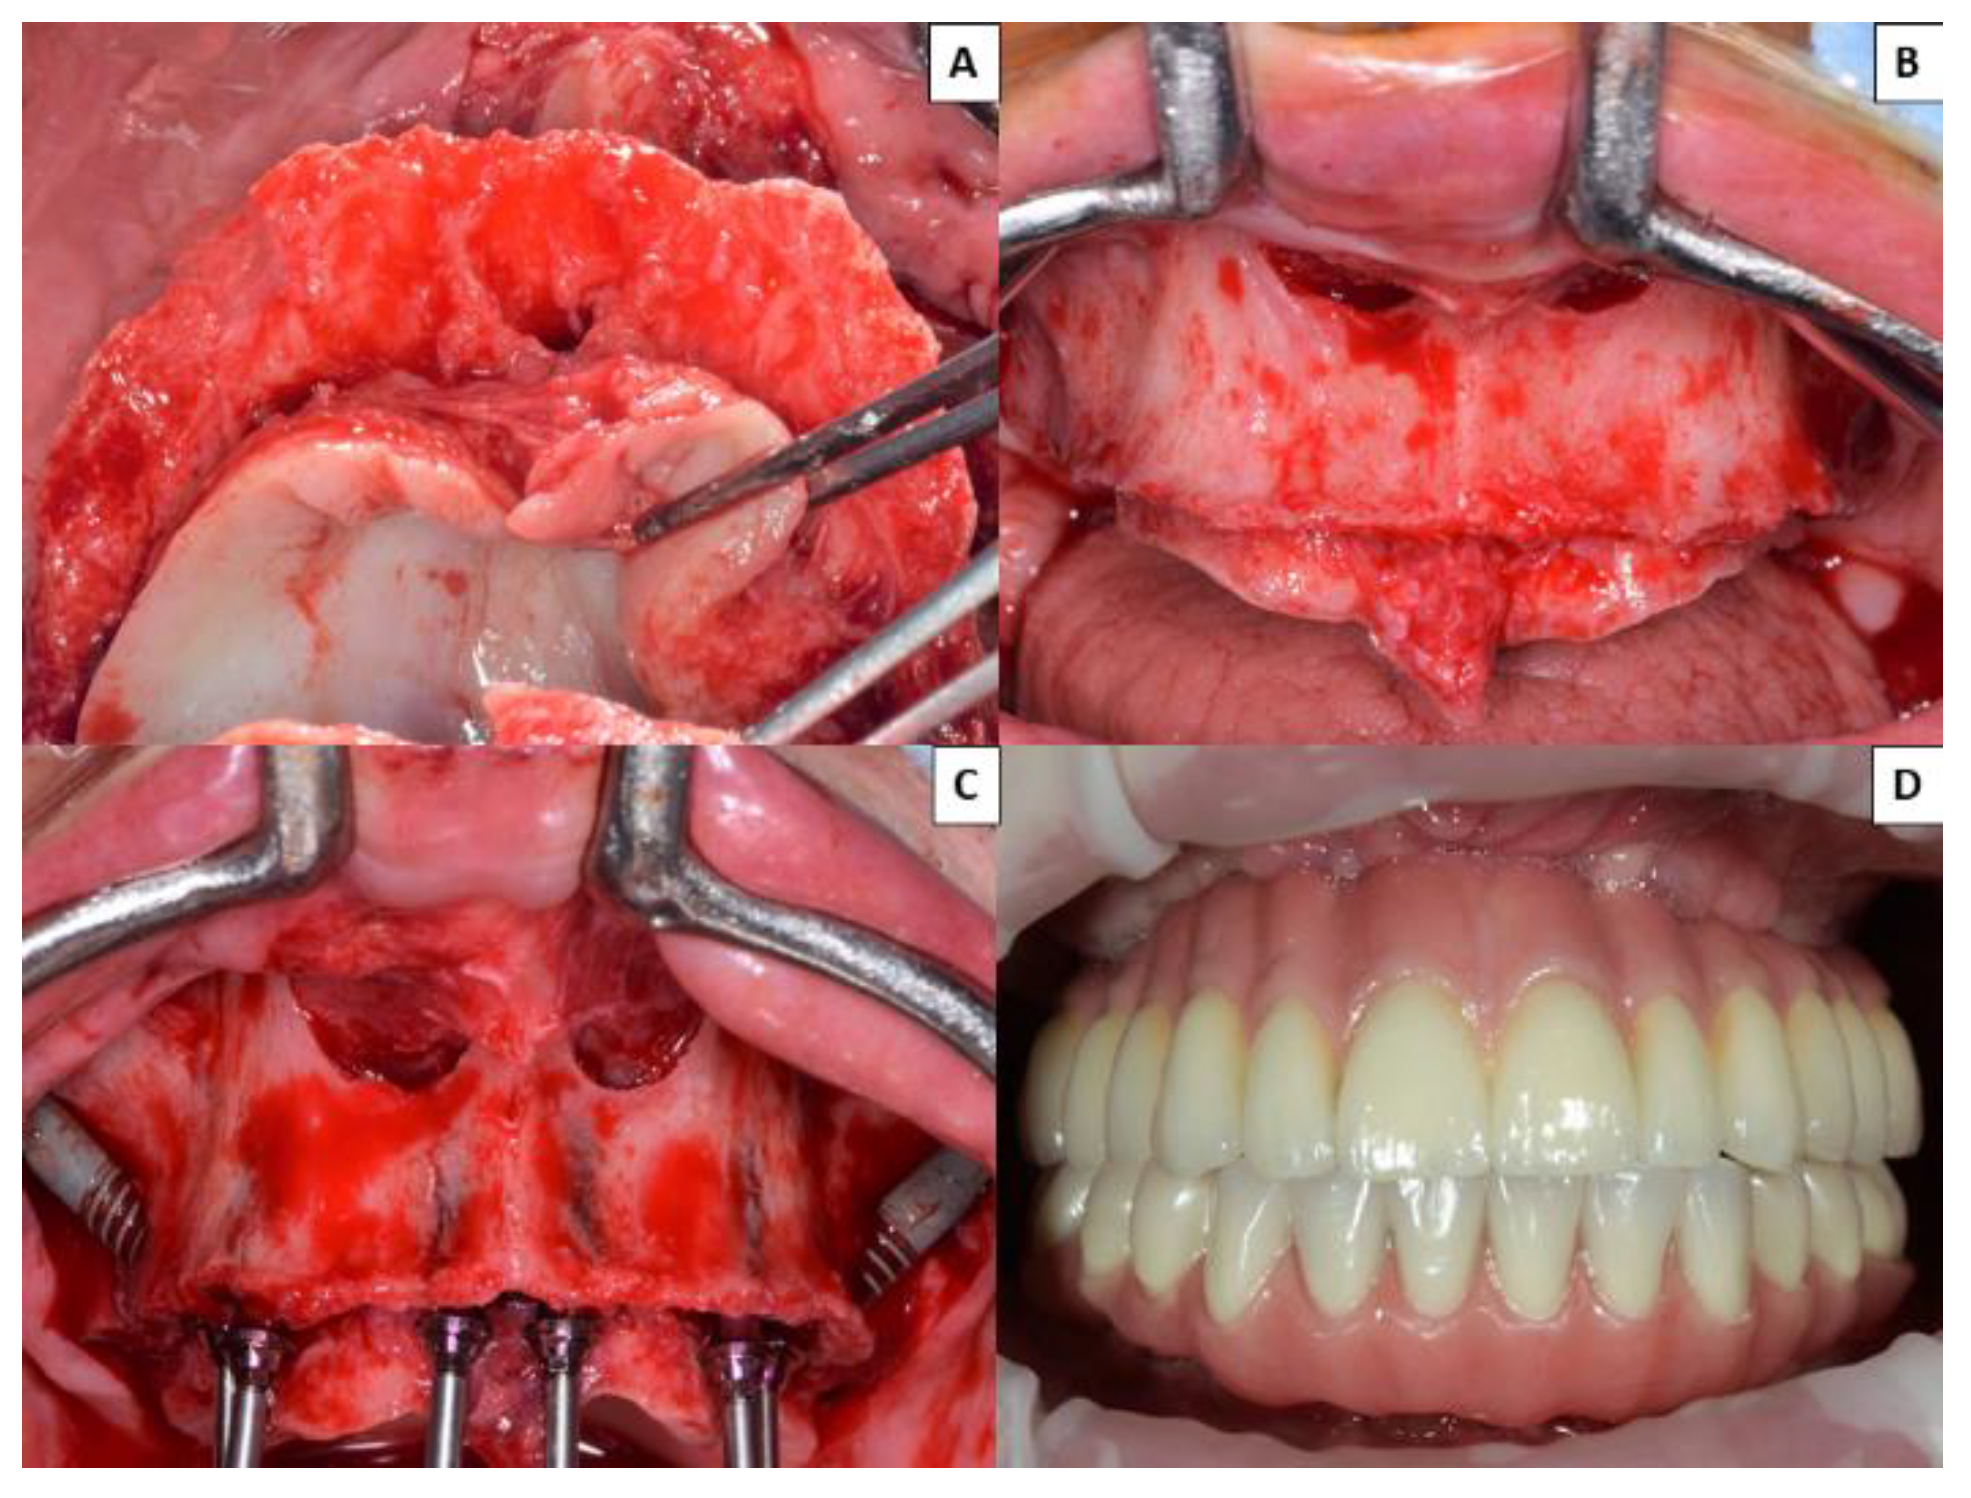

No prosthetic complications were recorded in Group 1 patients rehabilitated with zygomatic implants (either in provisional or definitive prostheses) (Figure 2), while three of the 40 patients (7.50%) treated by means of the all-on-four concept suffered prosthetic fractures, and another five (15.50%) presented excessive accumulations of food trapped apical to the definitive prostheses (Figure 3). None of the implants of this study failed, resulting in an implant cumulative survival rate of 100%. The cumulative survival rate for prostheses was 96.25%.

Figure 2. Group 1 patients with atrophic maxilla rehabilitated with two zygomatic implants and four conventional implants in the premaxilla. (A) Occlusal image of severe atrophied maxilla. (B) Front view of atrophic maxilla. (C) Placement of two zygomatic implants and four conventional implants in the anterior region. (D) Fabrication of definitive fixed prosthesis 6 months after surgery.